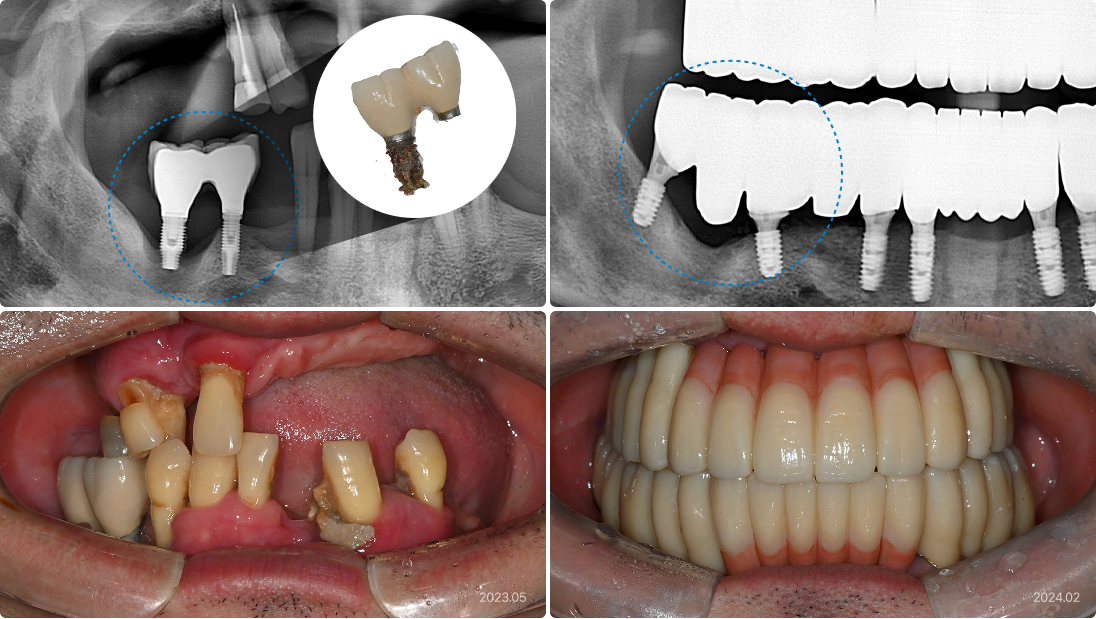

63세, 남 잘못된 치료 계획으로 인한 잇몸 문제

“임플란트 주변 잇몸이 계속 붓고 피가 나요.”

치료 전

• 적절하지 못한 크기와 잘못된 위치의 임플란트가 염증과 실패 유발

• 충분한 수의 임플란트임에도 불구하고 전부 다 연결되어 있어서

관리 및 치료가 불가능

• 하루라도 치아가 없이 지낼 수 없는 사회적 위치에서 위 턱의

모든 임플란트와 치아를 제거해야 하는 어려운 상황

치료 후

• 3D CT로 사전에 잇몸 뼈 상태를 정밀하게 분석, 재식립할 위치와

치료 계획 설정

• 수면 마취 하에 위 턱의 모든 임플란트와 보철물을 제거, 염증 깨끗하게

긁어냄

• 전악을 즉시 재식립, 디지털 임플란트 시스템으로 하루 만에 고정성

임시치아 장착

60세, 여 잘못된 보철

“보철물이 잘 안 맞고, 염증이 자꾸 생겨요.”

• 임플란트 보철이 잘못 제작되어 경계 부위가 벌어짐

• 유해 세균이 모이고 증식할 수 있는 틈이 되어 염증 발생

• 염증이 심화되어 잇몸뼈 흡수, 악취 및 통증 유발

• 기존 임플란트와 염증 조직 깨끗하게 제거

• PRF(자가혈이식재)를 동반한 뼈이식 동시 진행, 잇몸뼈 재건

• 보철물 적합 시 경계부가 부드럽게 이어지도록 철저히 확인